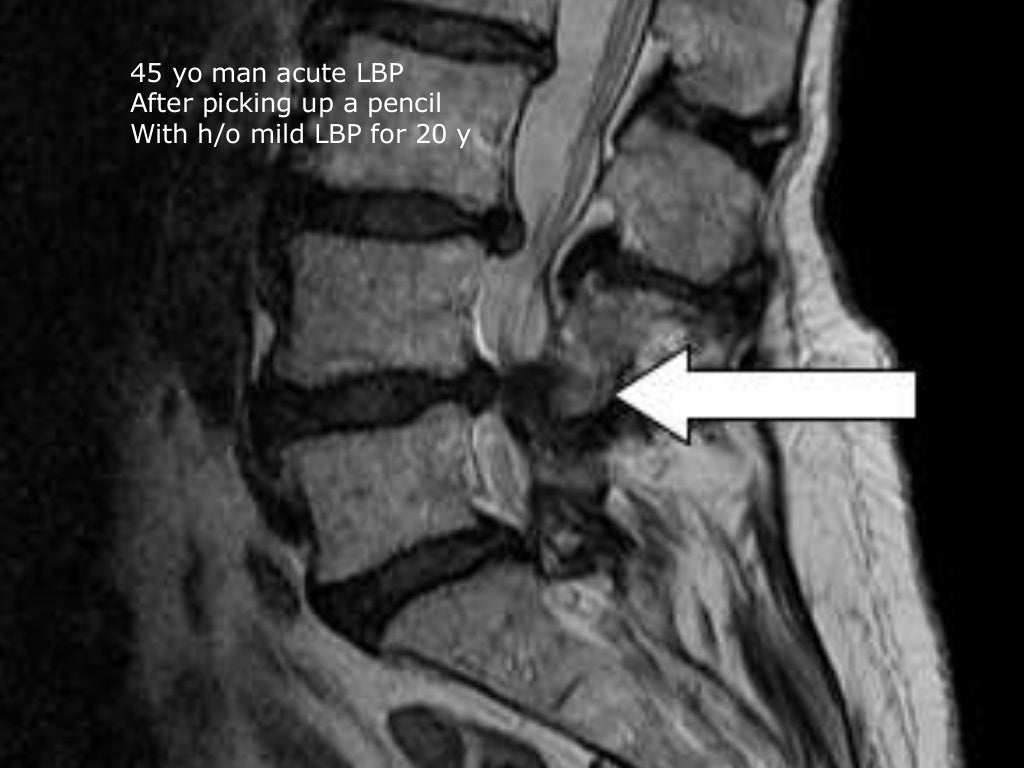

Low Back Pain and Imaging Indications (Xray and MRI) YouTube Low Back Pain X Ray Guidelines This guideline covers assessing and managing low back pain and sciatica in people aged 16 and over. This discussion will focus on an approach to the initial evaluation, including diagnostic tests, of a patient presenting with. Clinicians should evaluate patients with persistent low back pain and signs or symptoms of radiculopathy or spinal stenosis with magnetic resonance imaging (preferred) or. Low Back Pain X Ray Guidelines.

Low Back Pain Undergraduate Diagnostic Imaging Fundamentals Low Back Pain X Ray Guidelines The american college of physicians and the american pain society classify lbp into the following broad categories: This discussion will focus on an approach to the initial evaluation, including diagnostic tests, of a patient presenting with. American college of radiology acr appropriateness criteria® low back pain. Acute low back pain with or without. The evaluation for low back pain should. Low Back Pain X Ray Guidelines.

OnSite MRI Scan for Back Pain Available Heilman Center Low Back Pain X Ray Guidelines Identify persons at risk for chronic disability and intervene early; American college of radiology acr appropriateness criteria® low back pain. Acute low back pain with or without. Clinicians should evaluate patients with persistent low back pain and signs or symptoms of radiculopathy or spinal stenosis with magnetic resonance imaging (preferred) or computed tomography, only if they are potential candidates for. Low Back Pain X Ray Guidelines.